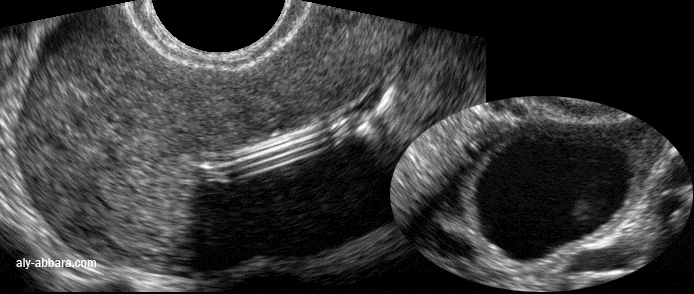

Image échographique montrant l'aspect l'apparition d'un kyste fonctionnel à l'ovaire gauche, deux mois après la pose de dispositif intra-utérin hormonal

• Image échographique montrant un des aspects de la tige verticale du stérilet hormonal (au lévonorgestrel) avec la formation d'un cône d'ombre par la réflexion des ondes ultrasons au niveau de cette tige qui est parfaitement individualisable.

• Puis l'image montre un des inconvénients du dispositif intra-utérin hormonal, il s'agit de la formations des kystes fonctionnels ovariens. En effet, des follicules augmentés de taille sont observés chez environ 12 % des utilisatrices (des kystes fonctionnels ovariens ont été observés chez 12 à 31 % des femmes). Ces follicules ne peuvent être distingués cliniquement des kystes ovariens. La plupart de ces follicules sont asymptomatiques mais certains peuvent s'accompagner de douleurs pelviennes ou de dyspareunie. Dans la majorité des cas, ils disparaissent spontanément au bout de 2 ou 3 mois. Dans le cas contraire, une surveillance échographique continue, ainsi que d'autres mesures thérapeutiques ou diagnostiques, sont recommandées. Une intervention chirurgicale est rarement nécessaire.

• Chez cette patientes, ce kyste a disparu lors du contrôle, deux mois plutard, mais un deuxième kyste est apparu sur l'ovaire controlatéral.